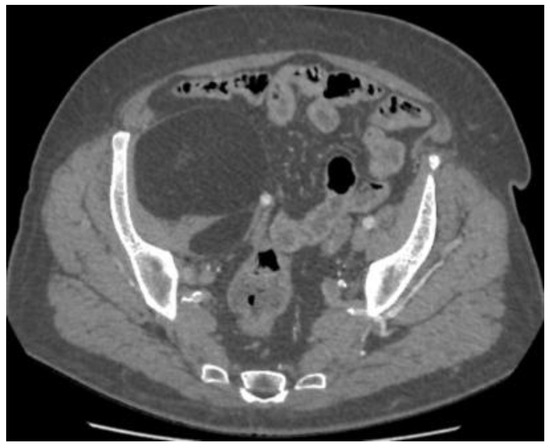

Asymptomatic Retroperitoneal Lipoma with Extension to the Right Anteromedial Thigh

2. Case Presentation